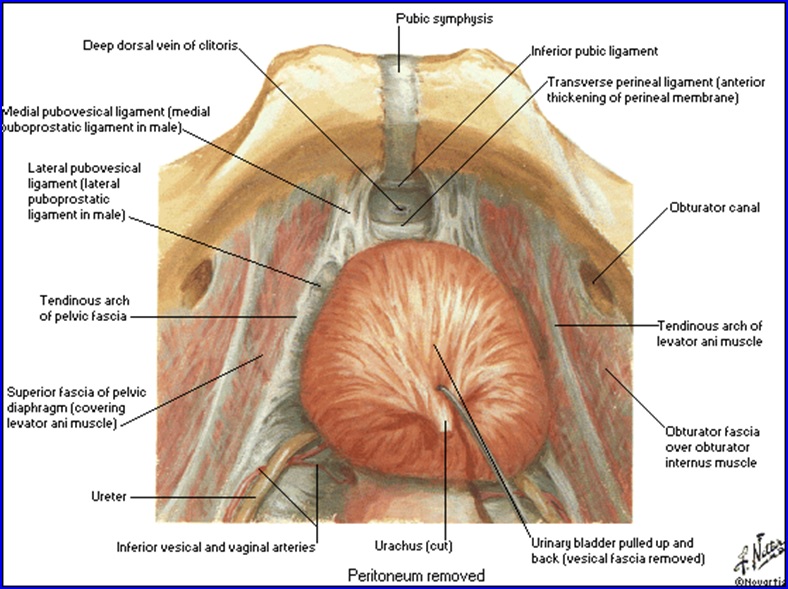

Vezica urinară la FEMEIE - orientare şi mijloace de susţinere (vedere superioară):